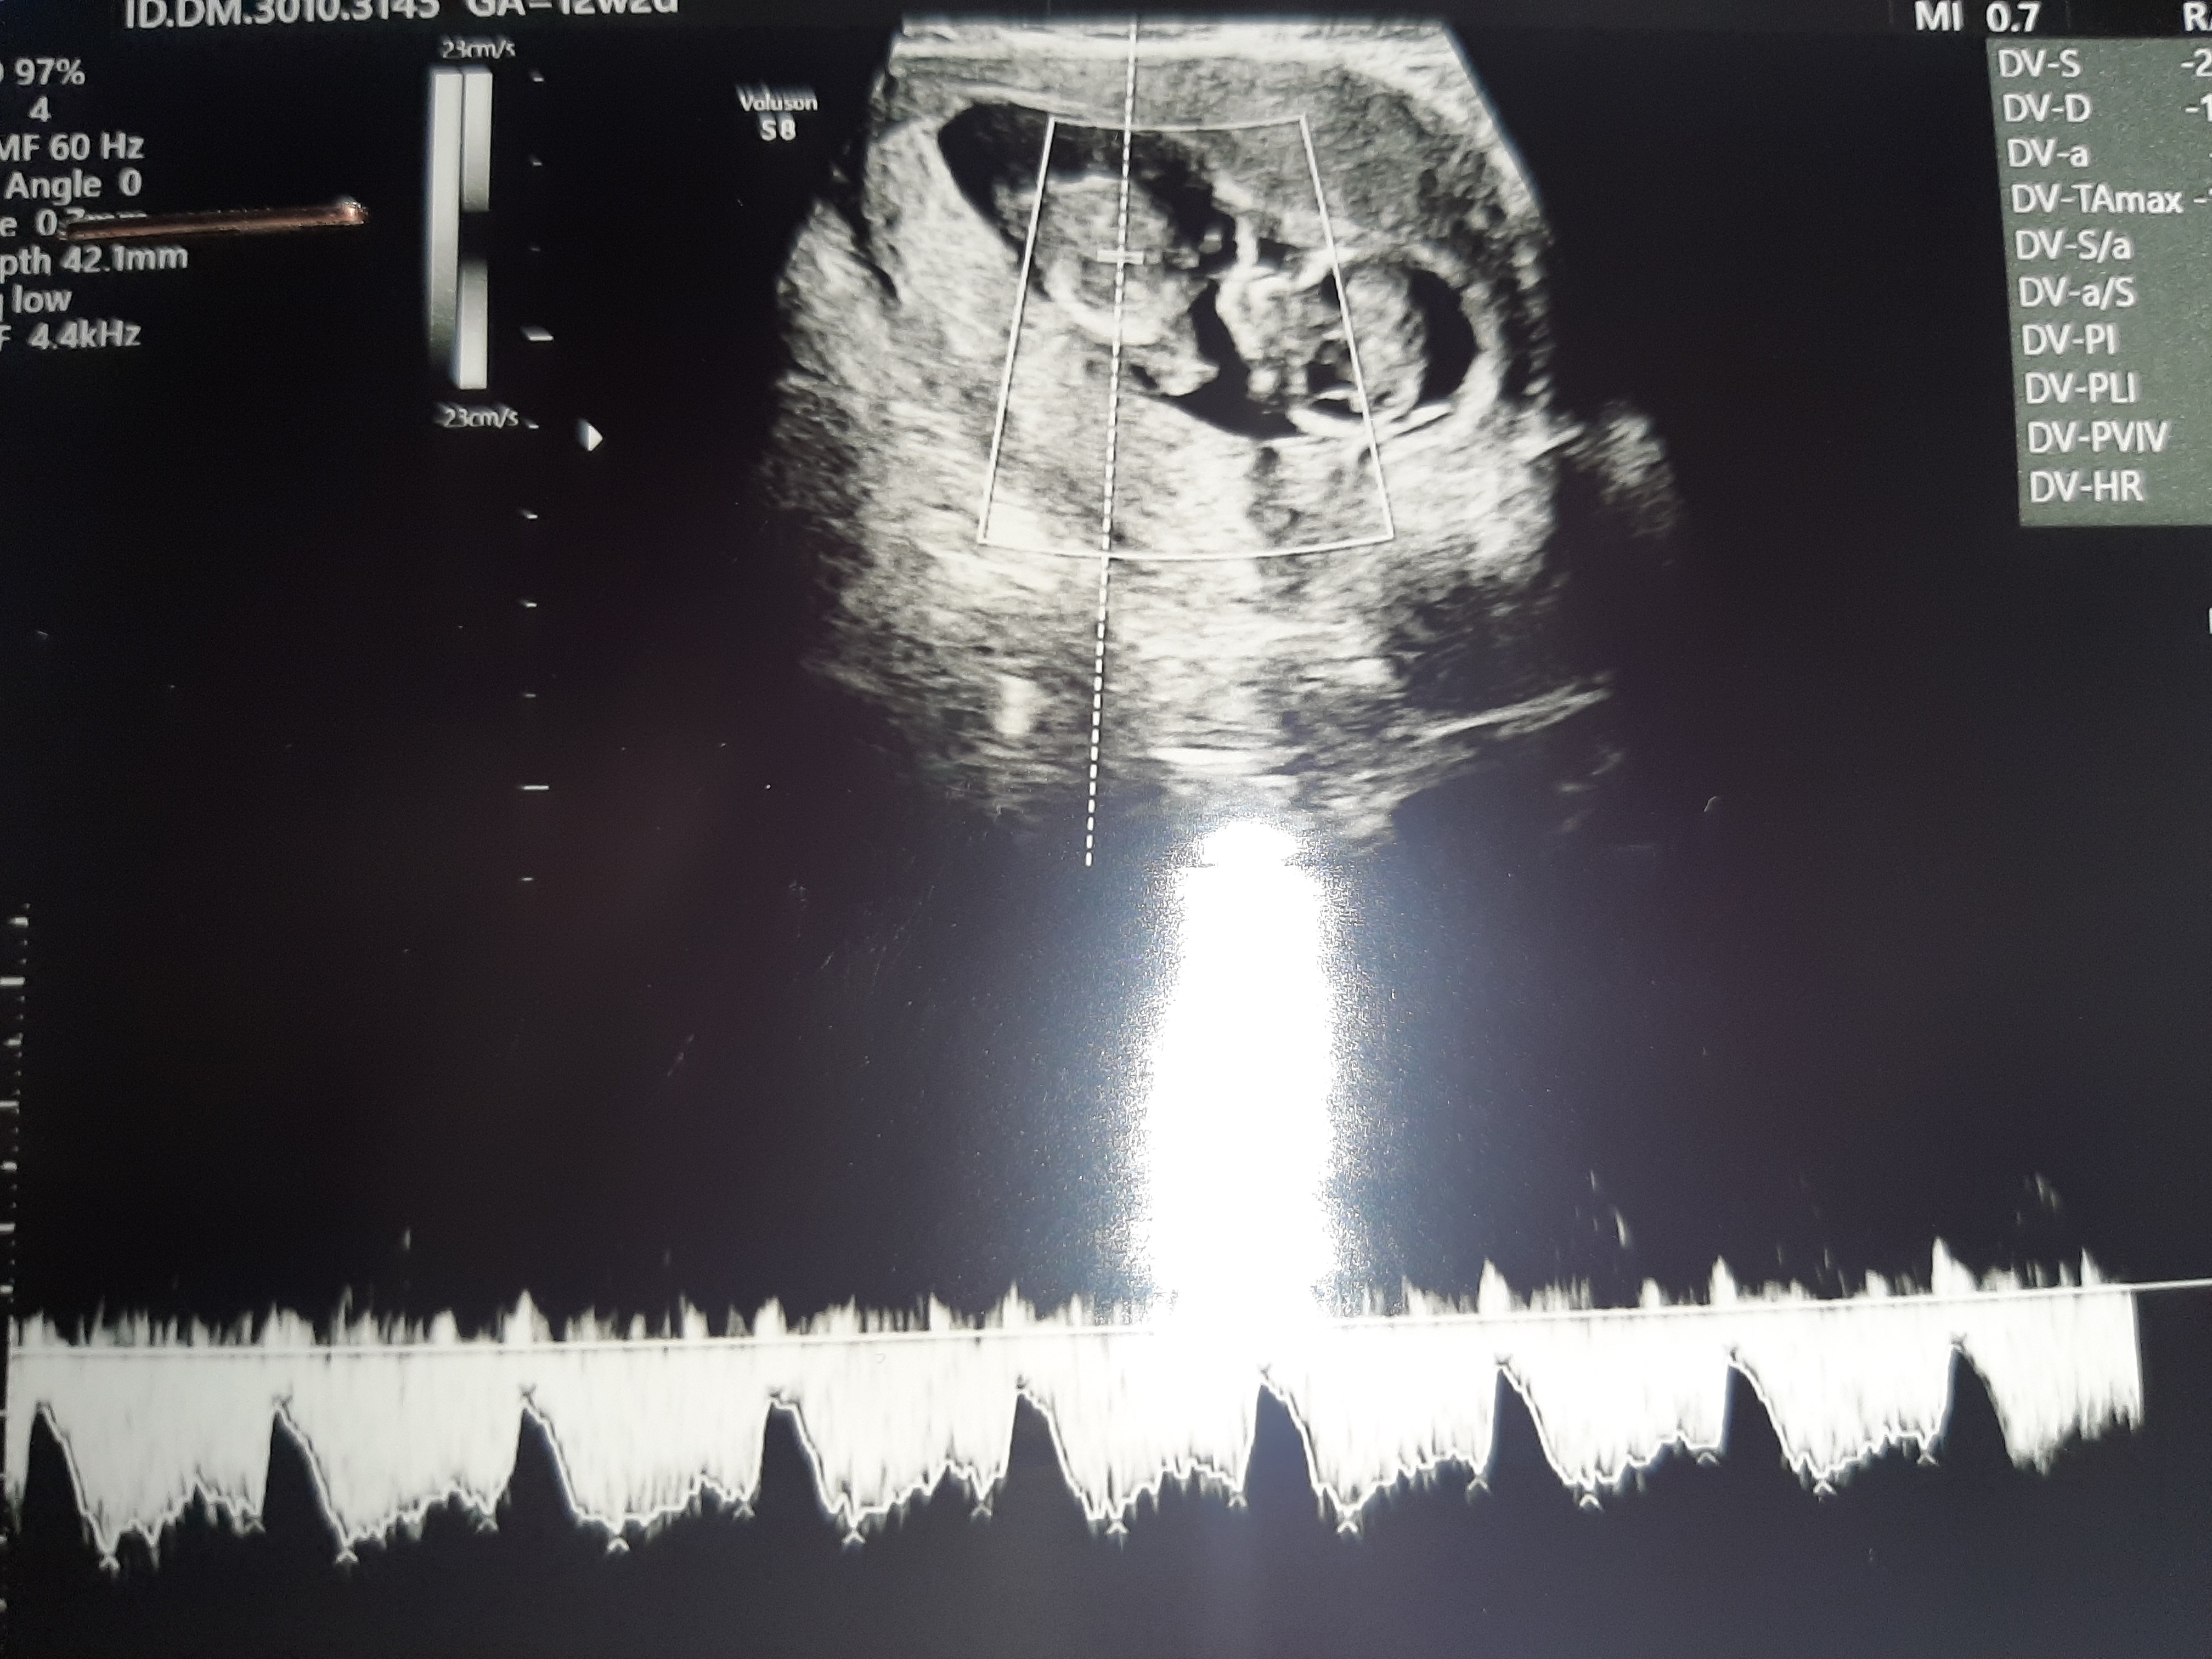

No dzisiaj mamy prawdziwą lawine dobrych wiadomości i oby tak dalej! SuperDziś miałam wizytę, na której dr robiła usg prenatalne, mówiła, że wszystko ok. W załączeniu wstawiam zdjęcia, chociaż one mi nic nie mówiąpo wizycie byłam na badaniu z krwi pappa w diagnostyce ale z tego wszystkiego nie zapytałam ile się czeka na wyniki. Kolej a wizytę mam 16 luty. A płci niestety jeszcze nie poznałam, mówiła że na kolejnej wizycie będzie można juz określić.